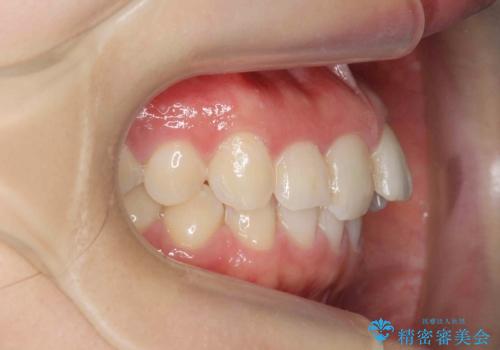

出っ歯に見える前歯の改善 部分ワイヤーとマウスピース矯正

- 出っ歯に見える前歯の改善を希望され、来院されました。

マウスピースでは改善の難しい歯の動きを部分ワイヤー矯正で整えたのち、奥歯の噛み合わせや細かい歯の並びをマウスピース矯正インビザラインで整えていきます。

最終的な前歯の並びに大変満足いただくことができました。